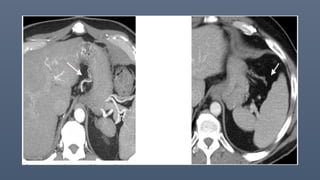

Intraperitoneal pseudomyxoma

peritonei due to appendiceal

mucinous adenocarcinomain a 66-

year-old woman.

Axial contrast-enhanced CT image of

the upper abdomen shows multiple

low-attenuation lesions involving

the lesser omentum (curved black

arrow); the gastrosplenic ligament

(straight black arrow); and

subhepatic, perihepatic, and

perisplenic spaces(white arrows).

The lesions cause mass effect on

adjacent structures and

characteristic “scalloping”of the liver

surface (arrowheads), in addition to

central displacement of small bowel

loops and the mesentery (not

shown).